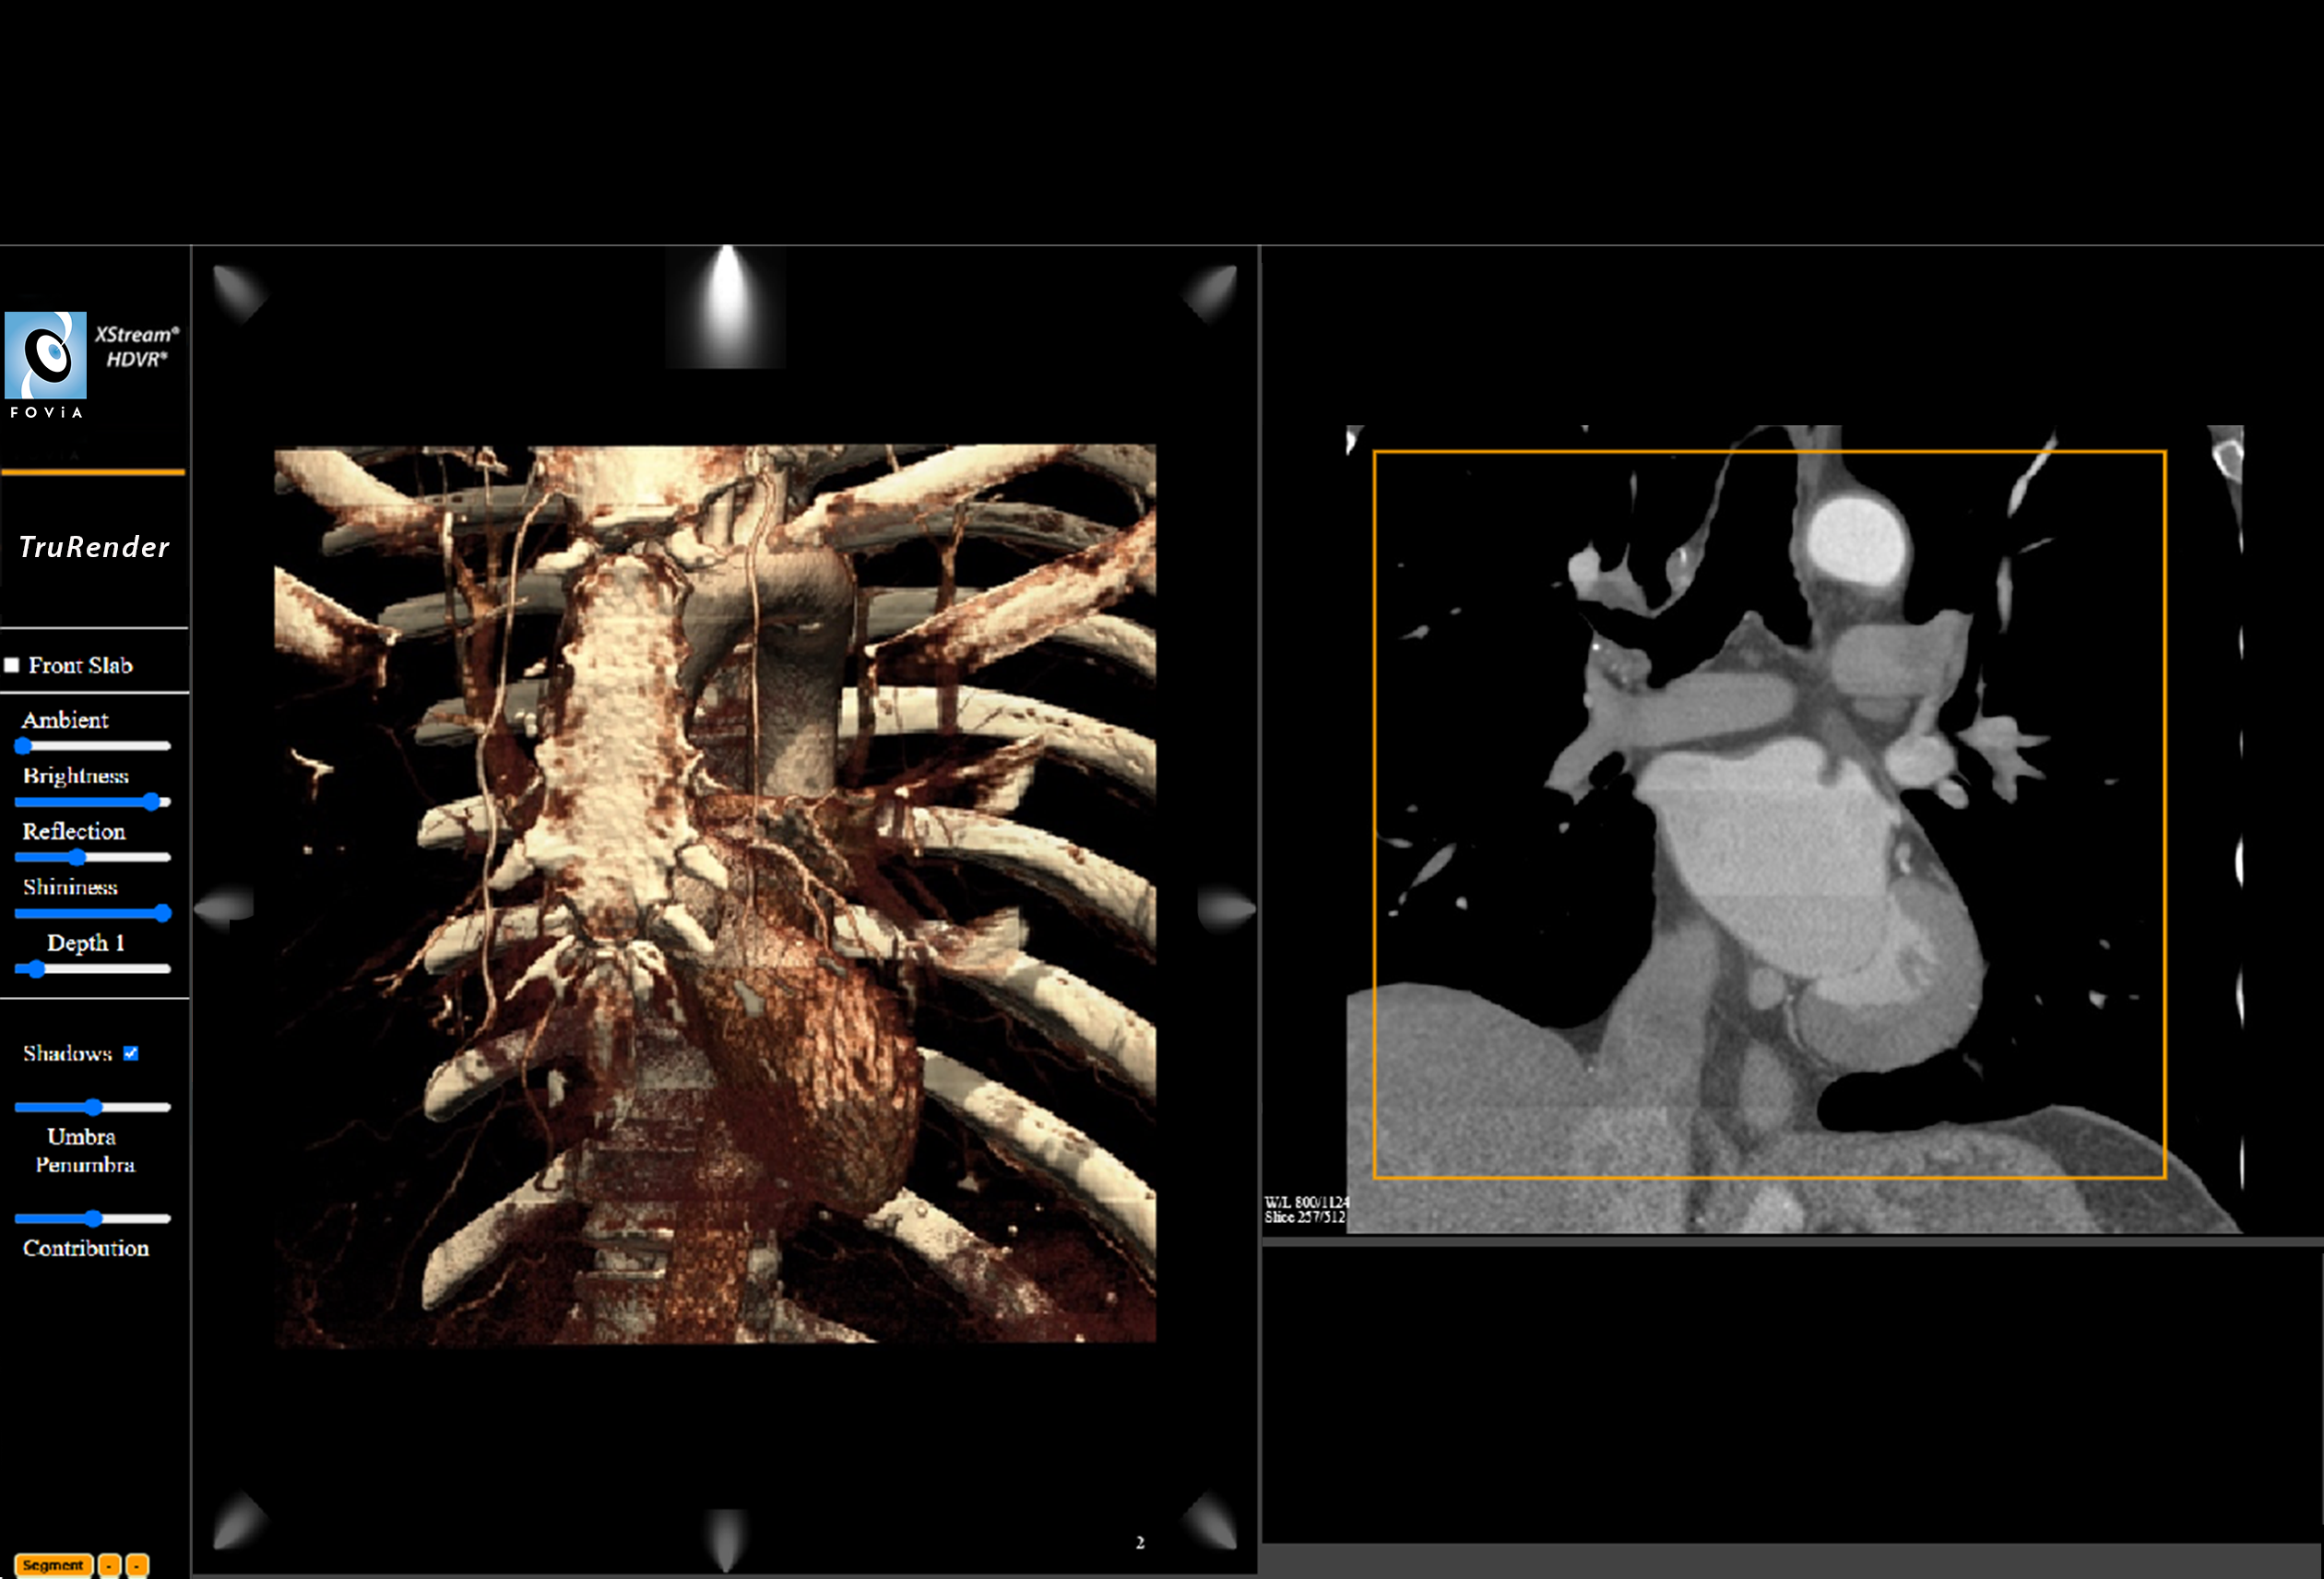

TruRender

TruRender